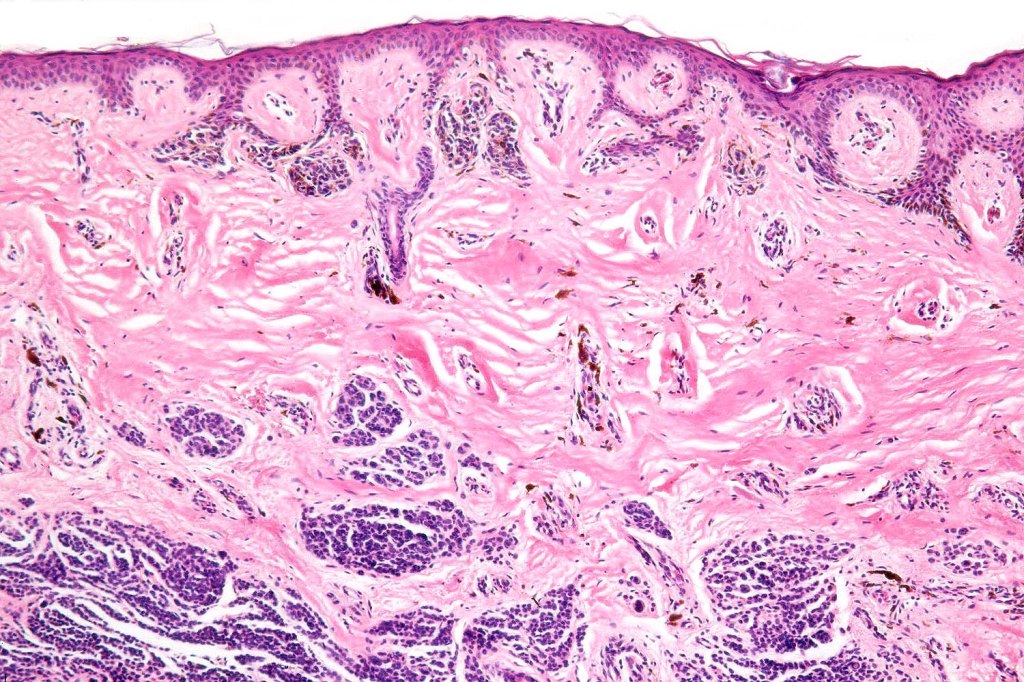

•Junctional/compound

•Large dyscohesive nests with retraction artifact, not restricted to the tips of the epidermal ridges

•Bridging common, often over multiple rete ridges

•Variable atypia (can be marked)

•Dermal fibrosis (sometimes lamellar)